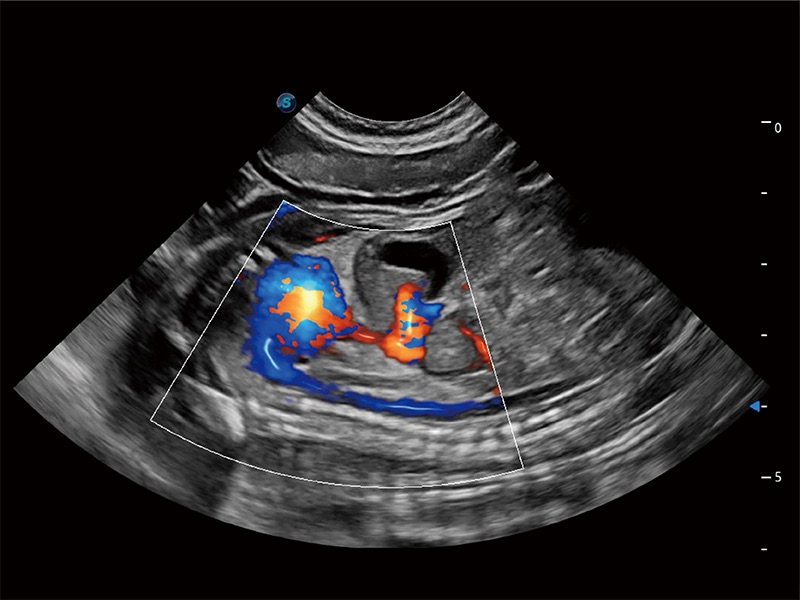

• Bright Flow 立体血流成像

在传统二维血流成像的基础上,呈现血流的立体感,具有动感的生命力之美。即便是微小的血管也能轻松应对,提高了血流的视觉敏感性。

(犬)胎儿主动脉弓立体血流

(犬)二腔心血流